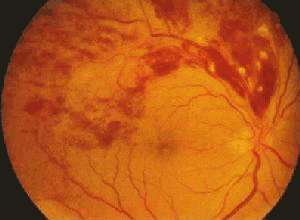

颞上支静脉阻塞

眼科,眼病,眼科图谱,眼病图片,眼底图谱,颞上支静脉阻塞